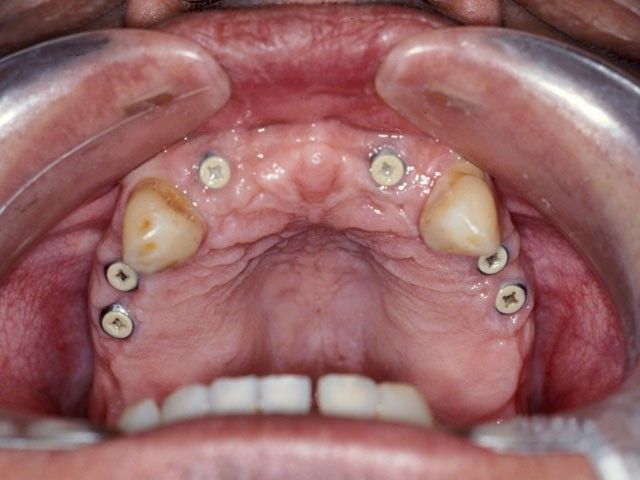

“Στις παρακάτω φωτογραφίες προβάλλονται δύο παλιά περιστατικά. Το πρώτο είναι το πρώτο μας εμφύτευμα και είναι το μακροβιότερο από όσα έχουν τοποθετηθεί στην Κρήτη! Το δεύτερο είναι μια μεγαλύτερη αποκατάσταση από το 1997”

ΔΕΥΤΕΡΟ ΠΕΡΙΣΤΑΤΙΚΟ